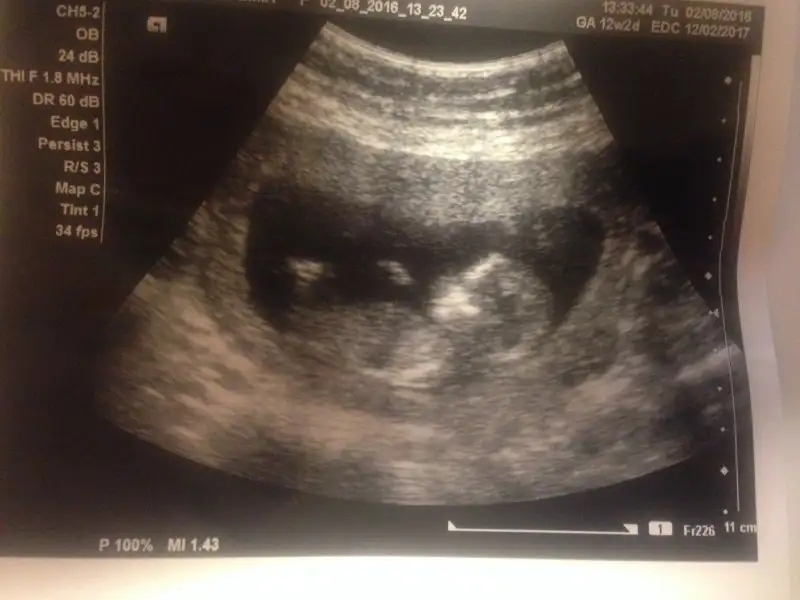

İlki cumartesi aldım ikincisi bugüne ait. Bugünkü çok karanlık.

cumartesi günkü yaptı erkek gibi dedi. ama bugünkü çok da uğraşmadı döndürmek için falan göstermiyor dedi. bu cumartesi tekrar kendi doktoruma gideceğim için de ısrar etmedim.Maşallah bebişe:) ben hiç anlamam ama 2. Resimde sanki baya erkek çocuğu görüyorum yaDr Bi yorum yaptı mı